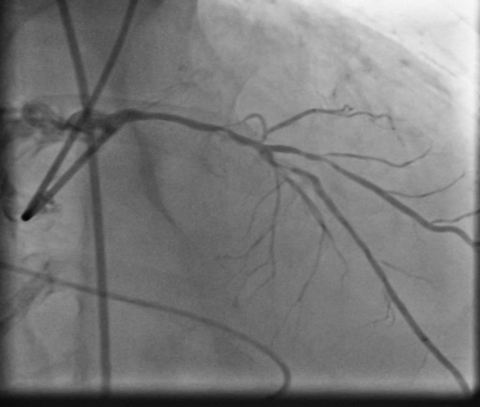

PCIof right coronary artery was initiated on IABP support with amplatz left1 guided catheter and vessel was crossed with great difficulty in repeatedattempts by fielder XT followed by GAIA 2 wire over corsair microcatheter. Microcathetercould not be crossed beyond mid segment calcified CTO, so balloon dilation with0.75 mm balloon was done after which again microcatheter could not be trackedbeyond mid part. Butwe were able to exchange wire to allstar followed by rotawire byplacing microcatheter in mid segment after balloon dilation by 0.75 mm balloon. Rotablation wasdone with 1.25 mm burr at 1,60,00 rpm repeatedly from proximal to mid distalpart. Lesionstill looked unprepared as repeated postdilation with2.25*15 mm followed by 2.5*15 mm non compliant balloon at high pressures showedunexpanded balloon. Againlesion preparation was done with 2.5*15 mm wolverine cutting balloon repeatedlyat high pressures which led to adequate luminal gain and calcium cracks as seenon IVUS run. AfterIVUS run again high pressure balloon dilation was done with wolverine 2.5*15 mmballoon followed by 2.5*12 mm non compliant balloon at 28 atm toadequately prepare the lesion before stent deployment. Stentingwas done with 2.5*32 mm DES, 2.75*32 mm DES, and 3*24 mm DES from distal toproximal in overlapping fashion. Thenfinally high pressure post dilation was done with 2.75*15 mm followed by 3*15mm non compliant balloon and adequate stent expansion was achieved with TIMI 3 flow.

Rightcoronary artery was well revascularized with adequate stent expansion and nosignificant complications. Patientwas weaned off from IABP support next day and regained his rhythm after 2 daysand then temporary pacemaker support was removed. Hewas planned for a staged rotablationguided PCI to left coronary system as he developed mild renal dysfunction whichgradually improved in hospital before discharge.